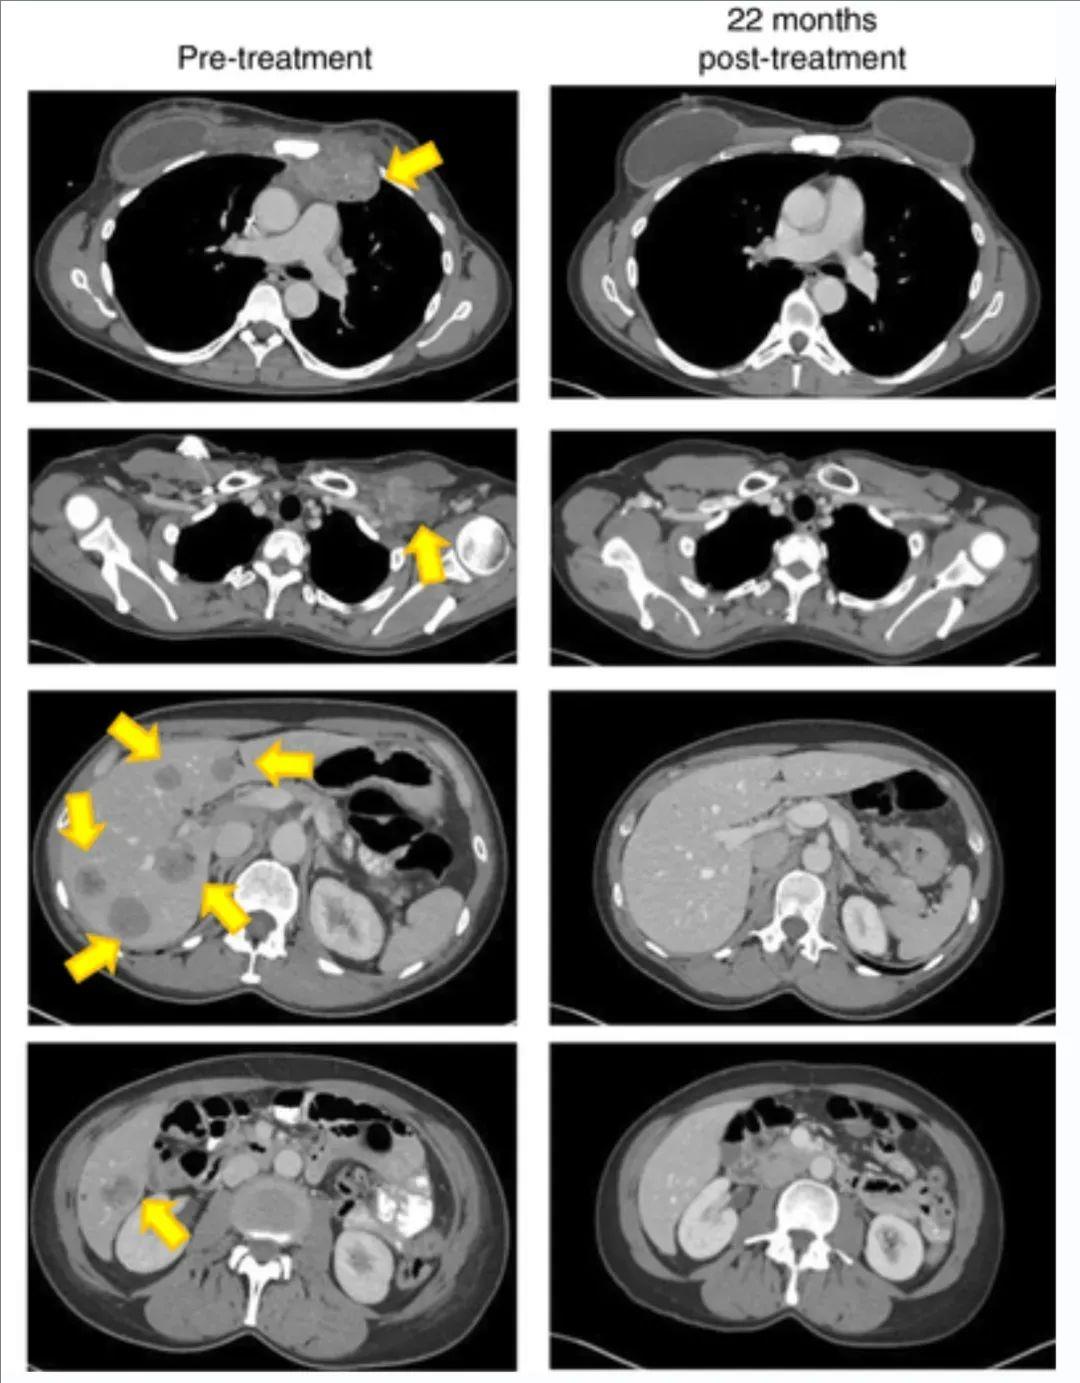

当900亿个免疫细胞被输入Judy体内后,奇迹出现了。TIL治疗1~2周后,胸腔内的肿瘤完全消失了!Judy在TIL回输治疗5个月后,2016年5月复查影像学显示,她的病灶竟然奇迹般的“消失”了(详见下图),肿瘤缩小到足以停止服用止痛药,而且生活也重回正轨。截至数据统计止,Judy已存活超过3年!她的经典案例也登上了顶级期刊《Nature》上,可以说TIL疗法,将Judy奇迹般地从死亡边缘拉了回来!如今她是全国乳腺癌联盟的倡导者,鼓励更多病友战胜癌症,重回正常生活!

▼TIL细胞治疗前、治疗后22个月的影像学对比

▲图源“Nat Med”,版权归原作者所有,如无意中侵犯了知识产权,请联系我们删除